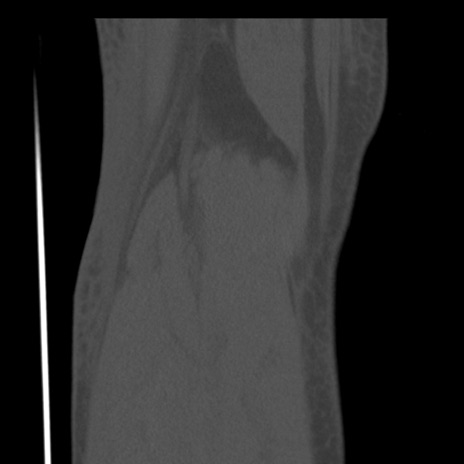

症例28 右膝関節CT(冠状断像)

右膝関節CT

矢状断像